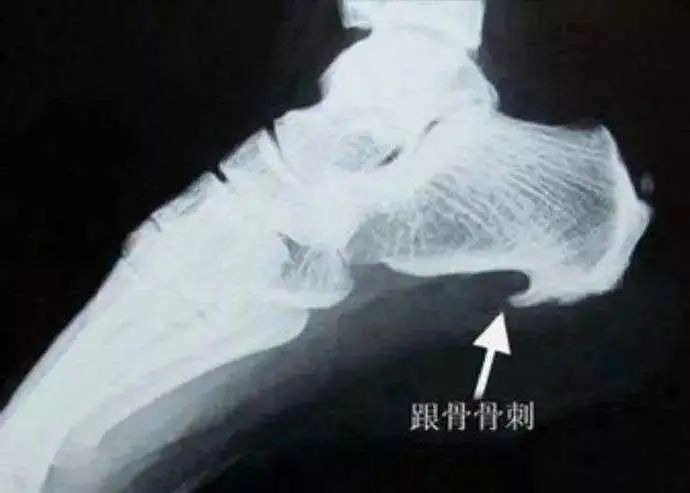

此结构最薄弱的部分就是“弓弦”与“弓体”相交接的地方,也就是足跟处,正是临床上最常见的骨刺发生部位。这个地方反复受到刺激和损伤,导致了在应力(弦)的方向骨刺的形成。所以我们仔细观察X光片会发现,骨刺方向是水平而不是垂直向下的。通过骨质增生的方式,增加韧带与骨骼的接触面积,减少骨骼单位面积上的受力,使得接触面更加稳定,重新变得平衡。